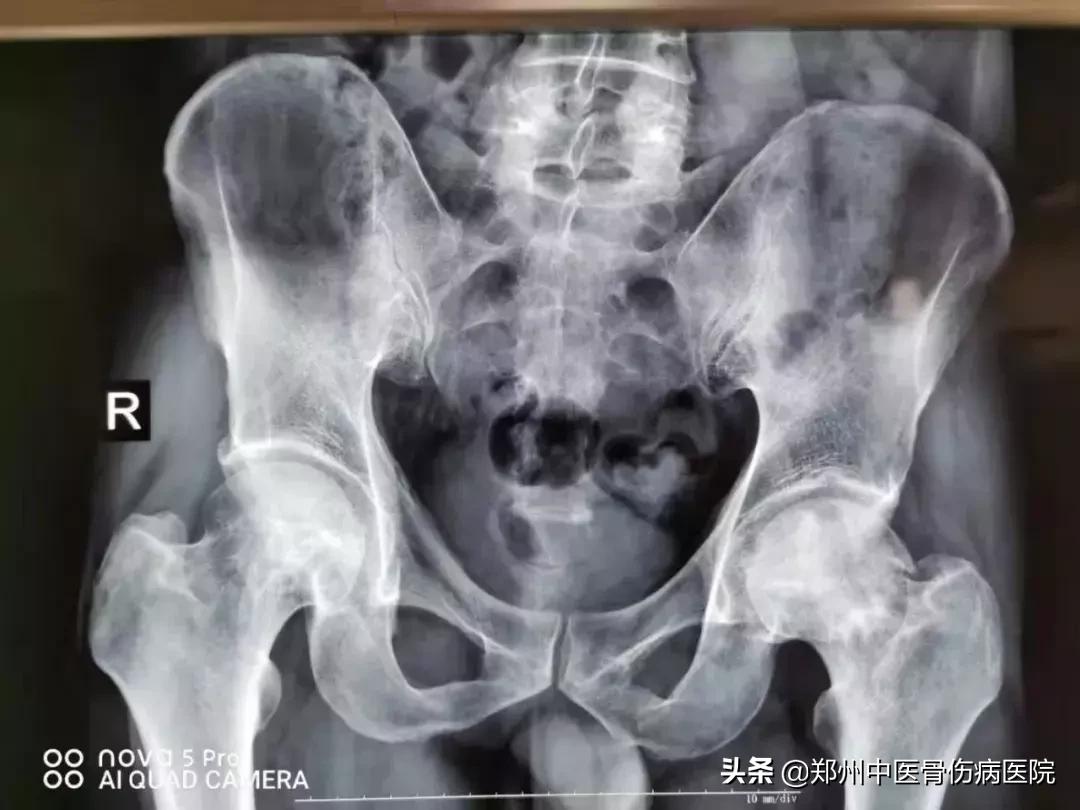

患者小王,女,32岁。右侧股骨头坏死II期,在家经常拄着一个拐杖做饭做家务,再加上走路时,左侧不敢用力而导致了骨盆不正,以致于整个脊柱偏歪,骨盆不正,下肢就会不等长,进而出现长短腿。